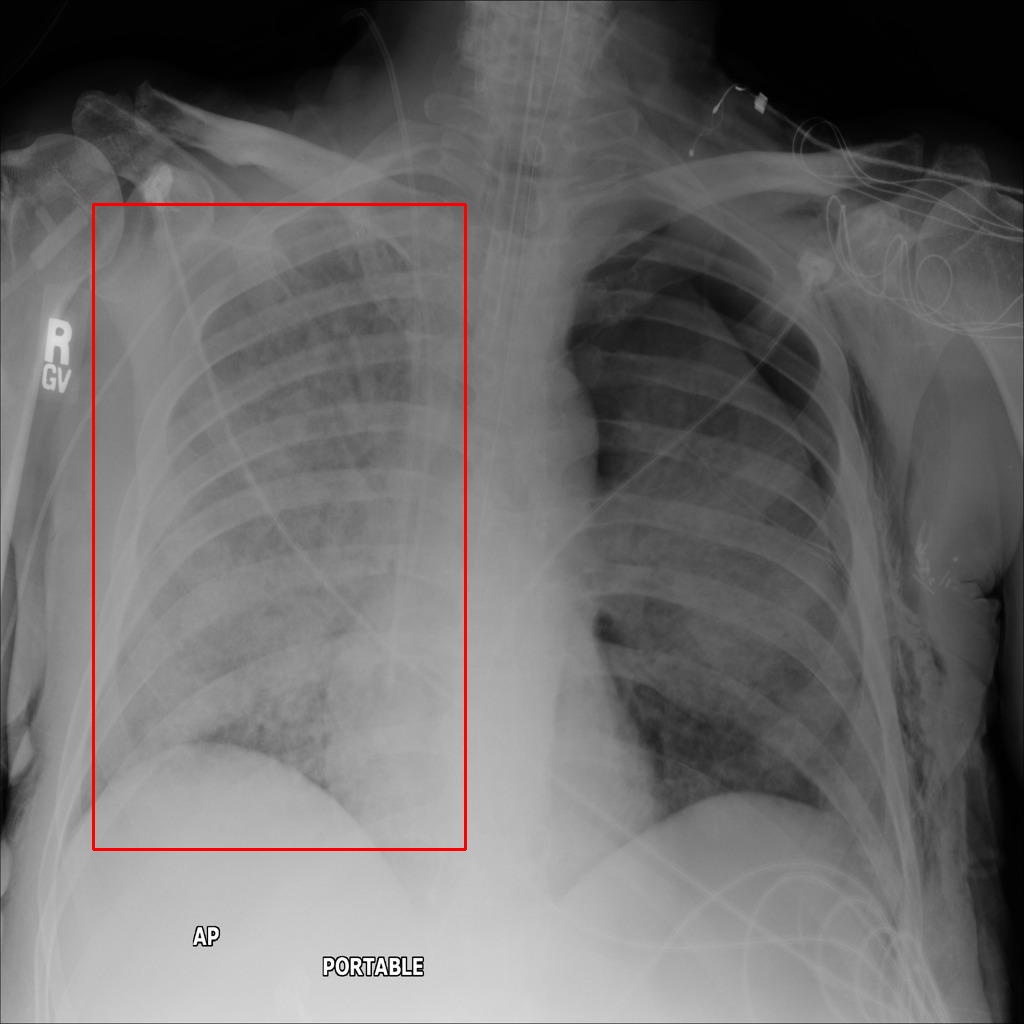

Refer to caption

(a) Normal

(b) Pneumonia 1

(c) Pneumonia 2

(d) Pneumonia 3

(e) Pneumonia 4

Figure 1: Examples of the five categories of X-ray images in the dataset, the first is a normal chest X-ray image without pneumonia, and the other four are images of four different types of pneumonia. The bounding boxes in the X-ray images are the area of the pneumonia lesions identified and marked by the doctor.